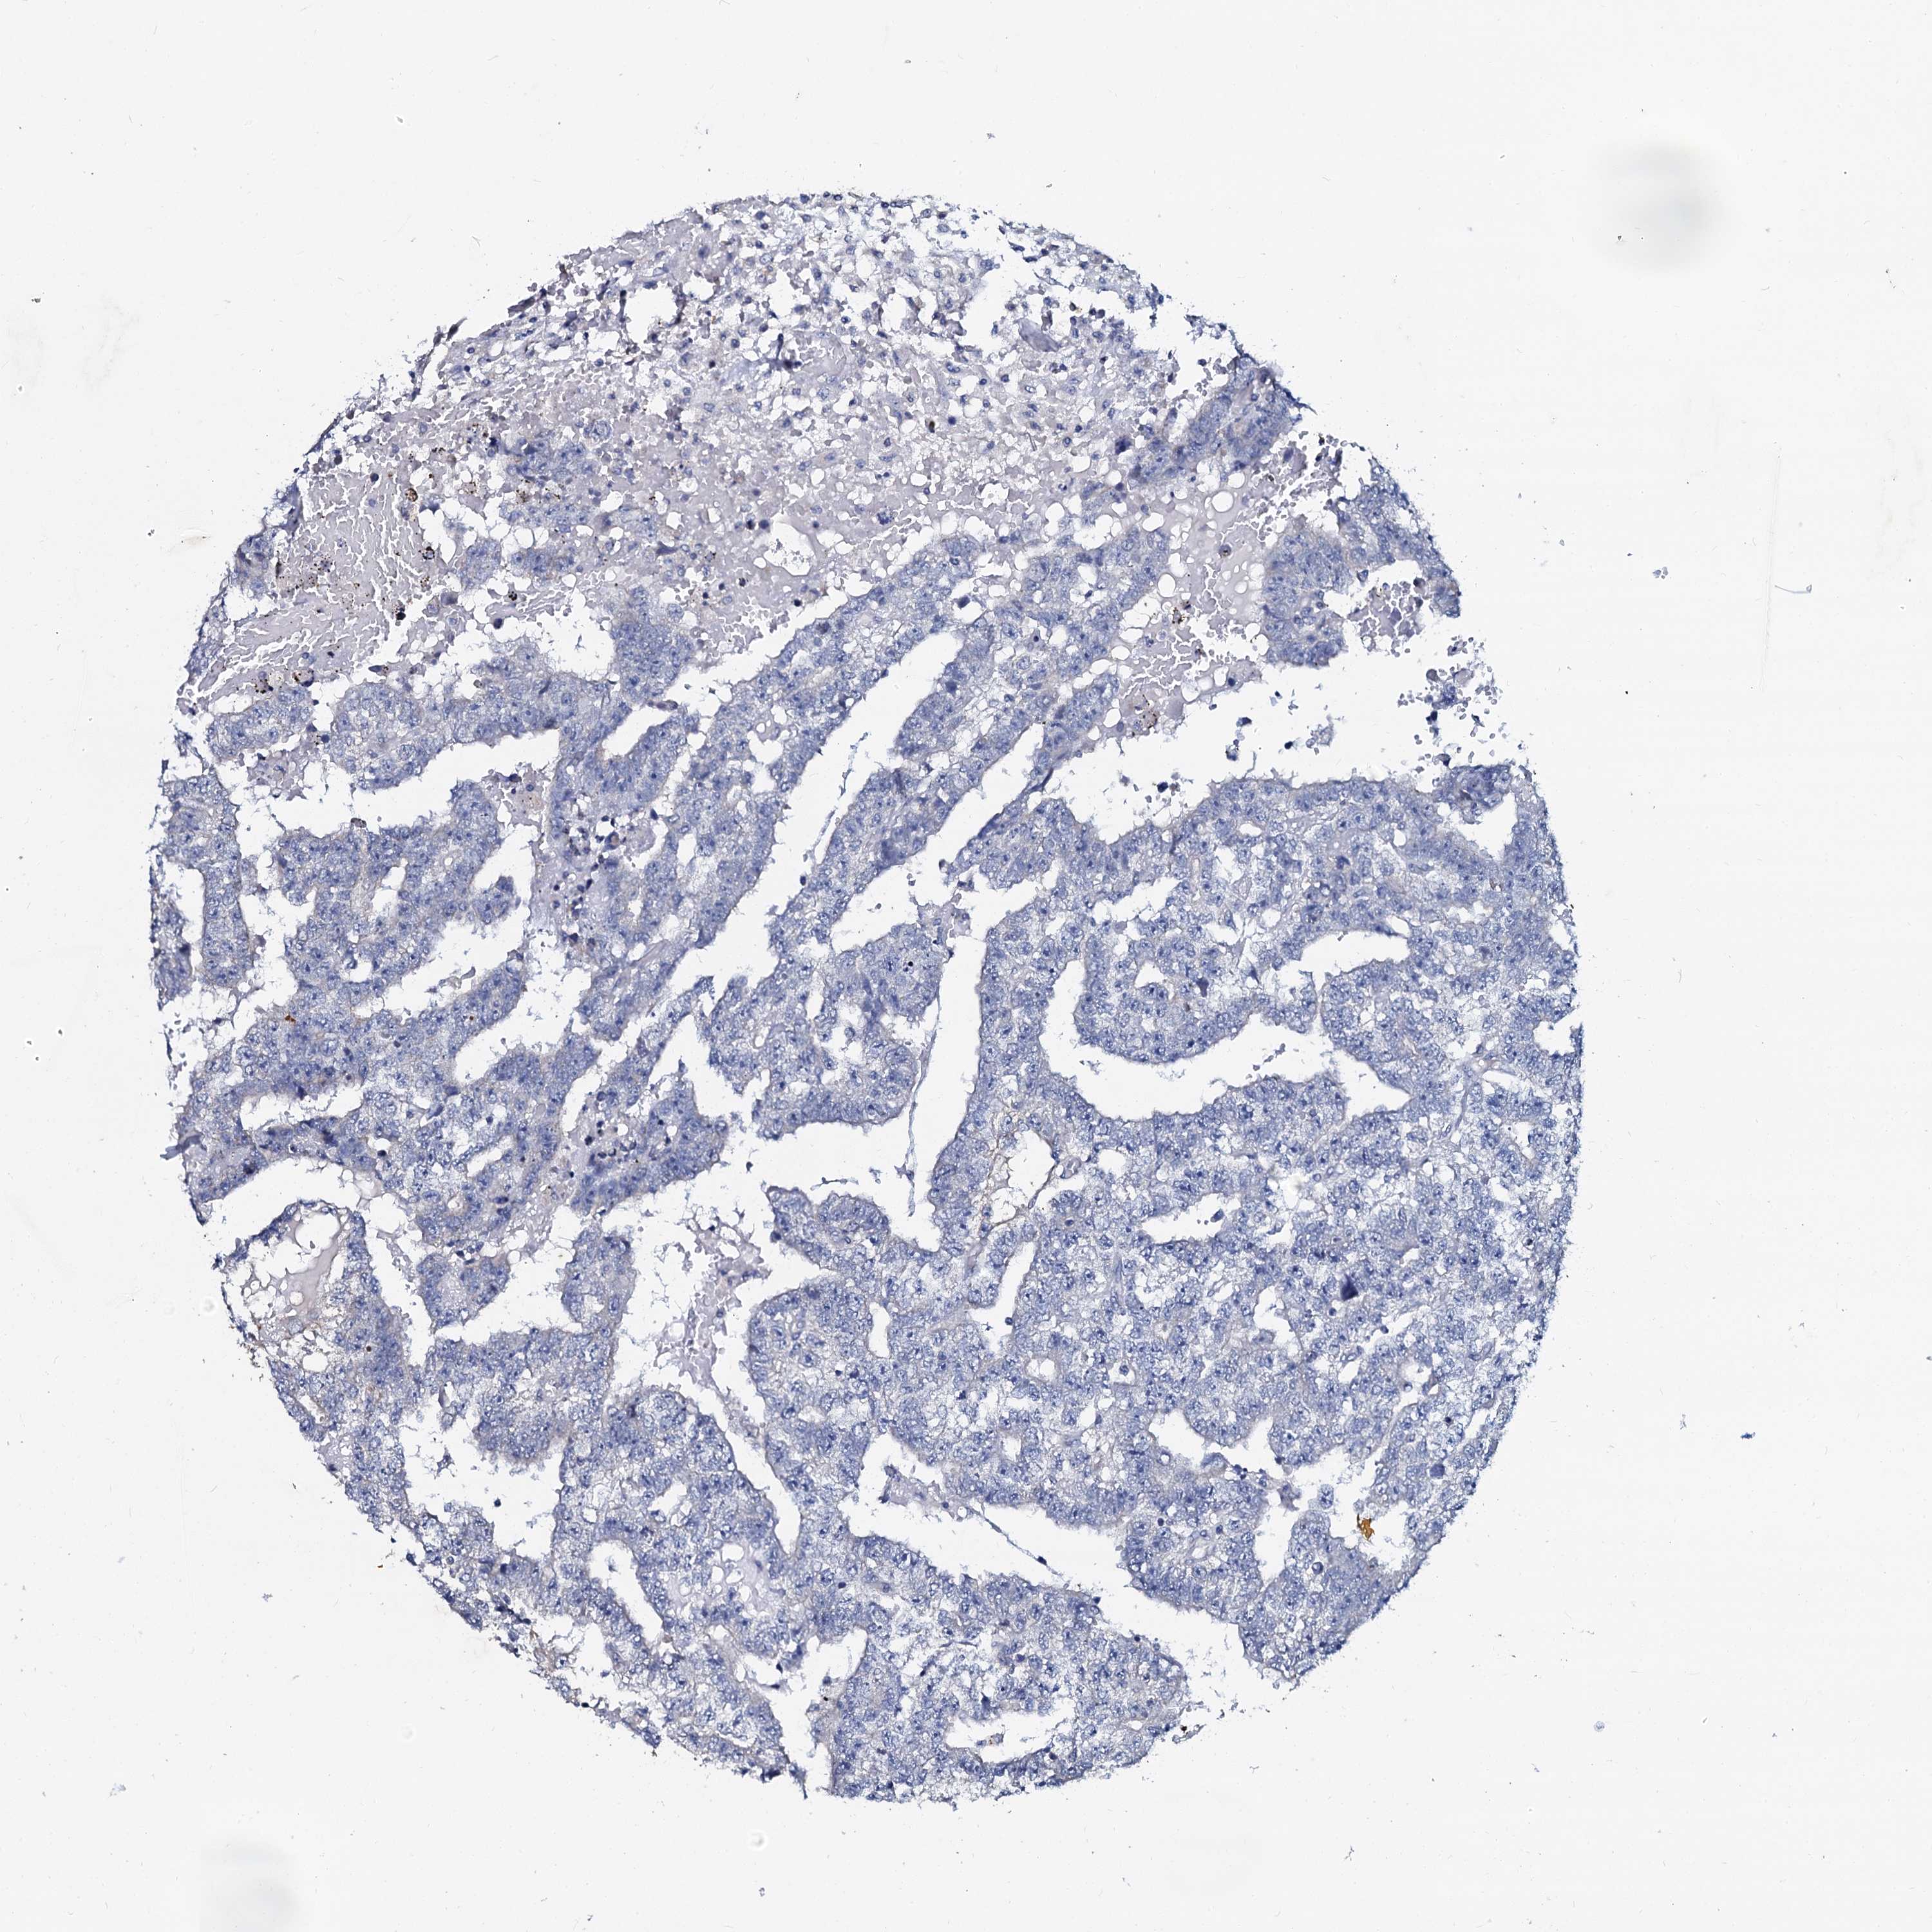

TESTIS CANCER - Protein expressioni

A mouse-over function shows sample information and annotation data. Click on an image to view it in a full screen mode. Samples can be filtered based on level of antibody staining by selecting one or several of the following categories: high, medium, low and not detected. The assay and annotation is described here.

Note that samples used for immunohistochemistry by the Human Protein Atlas do not correspond to samples in the TCGA dataset.

Antibody stainingi

Antibody staining in the annotated cell types in the current human tissue is reported as not detected, low, medium, or high, based on conventional immunohistochemistry profiling in selected tissues. This score is based on the combination of the staining intensity and fraction of stained cells.

Each image is clickable and will lead to virtual microscopy that enables deeper exploration of all samples and also displays staining intensity scores, fraction scores and subcellular localization as well as patient and tissue information for each sample.

Antibody HPA038939

Antibody HPA038940

Staining

High

Medium

Low

Not detected

Intensity

Strong

Moderate

Weak

Negative

Quantity

>75%

75%-25%

<25%

None

Location

Nuclear

Cytoplasmic/membranous

Cytoplasmic/membranous,nuclear

Carcinoma, Embryonal, NOS

Seminoma, NOS